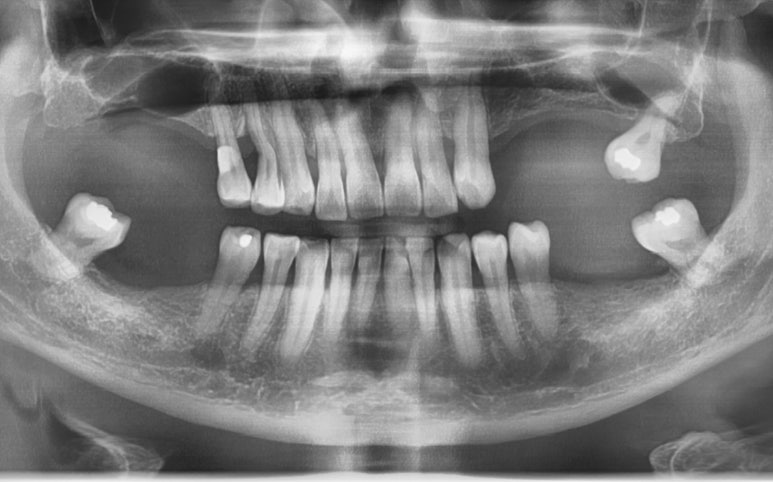

엑스레이를 촬영 해 보니 이미 큰 어금니는 싱가폴에서 많이 발치한 상태 였고

이번에는 작은 어금니가

가로로 파절된 것이 의심되는 확인할 수 있었습니다

치아 뿌리가 가로로 파절된 선이 보입니다

치아뿌리가 가로로 파절된 선이 보입니다

보이시나요?

표시해드릴게요 ↓